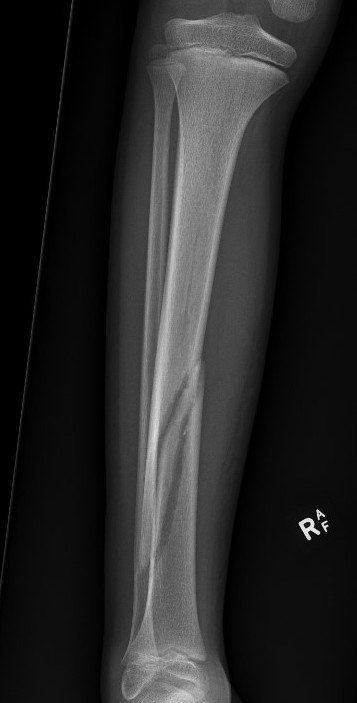

Proximal Metaphyseal Tibial Fracture / Cozen's Fracture

Issue

- may develop long term valgus alignment

- due to medial epiphyseal overgrowth / periosteum medially

Management

Any displacement

- MUA

- extension long leg cast with varus mould

Management of valgus

A. < 10 years with < 15o

- will usually remodel

B. > 10 years with > 15o

- consider operative intervention

- guided growth plates